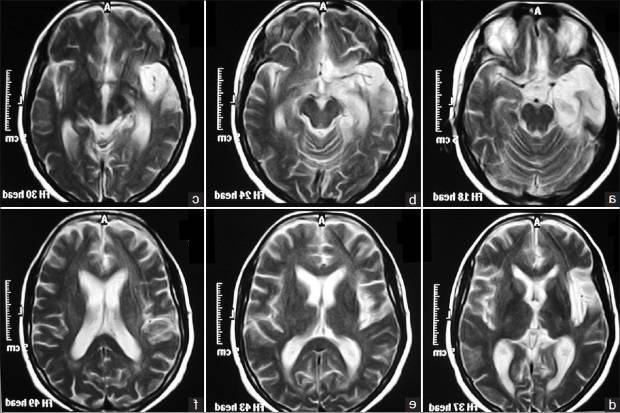

МР-признаки дисциркуляторной энцефалопатии

При возникновении вышеперечисленных симптомов стоит немедленно обратиться к невропатологу, который направит на дополнительные инструментальные исследования. Во время прохождения МРТ врач может заподозрить наличие дисциркуляторных изменений по специфическим МР – признакам:

- сосудистые гипотензивные включения;

- признаки гидроцефалии;

- наличие кальцинатов (атеросклеротических бляшек);

- сужение или закупорка позвоночных, базиллярных, сонных сосудов.

- Компьютерная и магниторезонансная томография мозга – данные исследования отражают наиболее полную картину состояния тканей мозга в момент проведения

| Магнитно-резонансная томография | Наиболее информативный метод диагностики микроинсультов в зонах ишемии |

- МР-ангиография при ДЭП определяет сосудистые гипотензивные включения, атеросклеротические бляшки, признаки гидроцефалии;